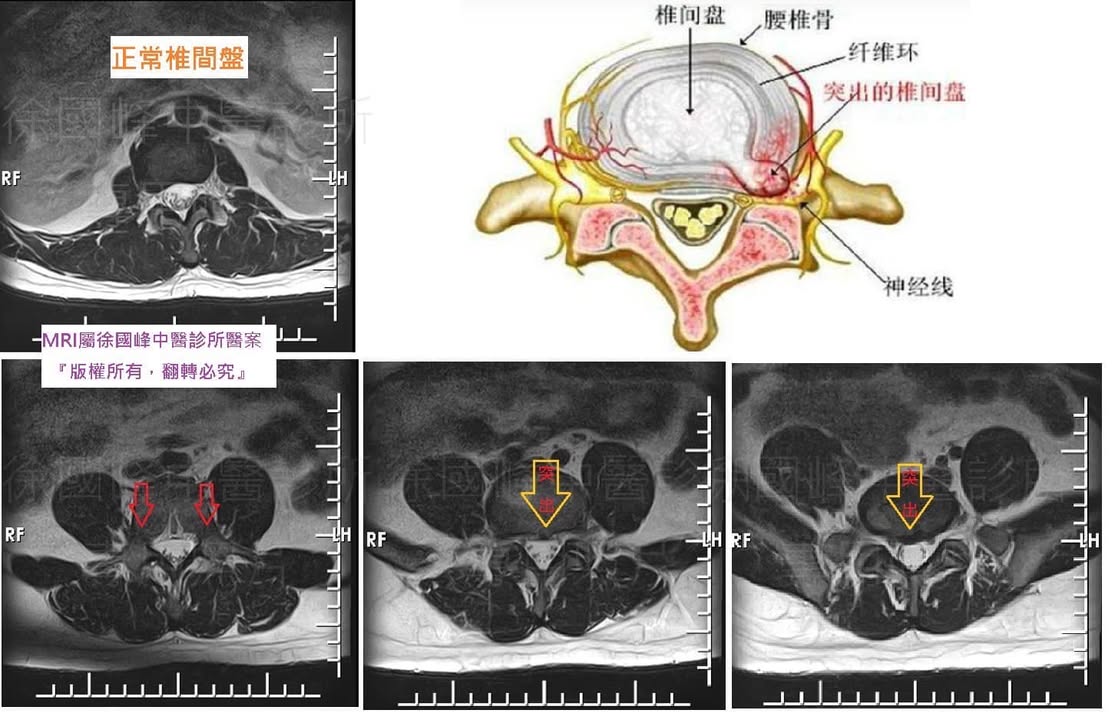

1.左側L4L5;L5S1 中重度椎間盤突出